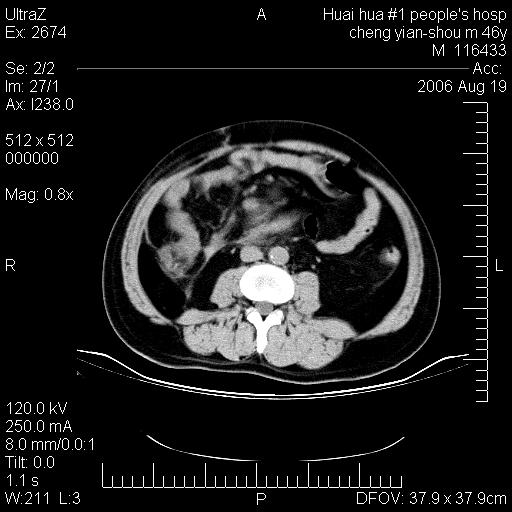

患者,男,46y。腹痛2月,消瘦。

十二指肠水平段占位,考虑间质瘤或平滑肌瘤。

肿块较大,腹膜后占位,境界欠清,周边脂肪密度较高呈条状影,有没有脂肪肉瘤可能,

缺少完整的三期图像。考虑肠系膜脂膜炎mp(肿块型)。

鉴别:间质瘤(这么大而无囊变不可思议)、平滑肌瘤/肉瘤、淋巴瘤、类癌,脂肪类肿瘤、转移瘤等。

十二指肠水平段占位,考虑间质瘤。

首先考虑小肠间质瘤。

十二指肠水平段软组织密度占位,考虑间质瘤可能性大。

腹膜后占位,境界欠清,考虑来源于十二指肠病变,间质瘤或平滑肌肉瘤可能性大。建议活检。